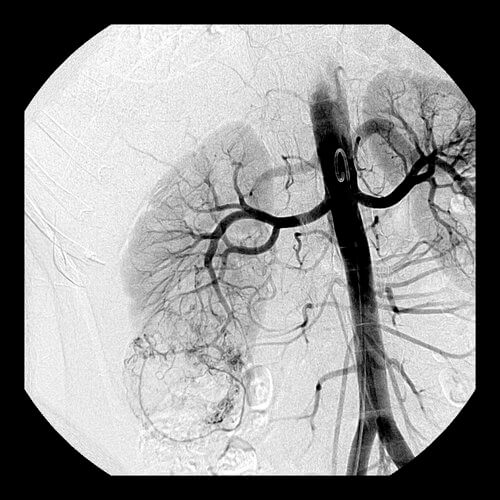

32 year old female who presents with an incidentally discovered right renal angiomyolipoma and undergoes prophylactic embolization.

Comment: This case demonstrates the classic appearance of an angiomyolipoma on CT and the hypervascularity associated with this benign tumor. The clearly seen abnormal vasculature enabled selective catheterization of the dominant supply to the angiomyolipoma and subsequent selective embolization with PVA particles. Embolization can be performed successfully with several types of particulate and/or liquid embolic agents. In this case, PVA was used successfully and no growth or viability has been seen on follow-up imaging after this procedure.